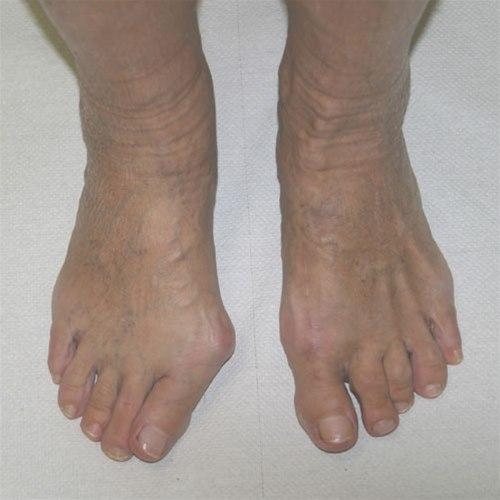

Hallux valgus før og etter operasjon.Hallux valgus er en feilstilling av stortåen (hallux) slik at den vris i retning lilletåen (valgus). Samtidig er stortåens grunnledd delvis ute av ledd og forskjøvet innover mot den andre foten. Typisk finner vi skjevhet i stortåen og sårhet over stortåens grunnledd. Leddet hovner opp og blir svært markert og prominerende på innsiden av foten, og det blir smertefullt og ømt. Forandringene i foten kan gjøre det vanskelig å finne sko som passer godt på foten.

De aller fleste opplever betydelig mindre smerter etter inngrepet, samtidig som stortåen er blitt markant rettere. Men det kan ta inntil et halvt år før foten fungerer så godt som den kan. Noen (ca. 10 prosent) opplever tilbakefall med ny feilstilling av foten og nye plager etter en tid. Dersom brusken i stortåens grunnledd er ødelagt, må leddet avstives (primær artrodese).

Operasjonen vil imidlertid ikke gjøre det mulig for deg å bruke mindre skostørrelse eller å bruke spisse sko. Man må være innstilt på å bruke fornuftige sko resten av livet. Følg rådene i omtalen av hallux valgus for utprøving av nye sko.